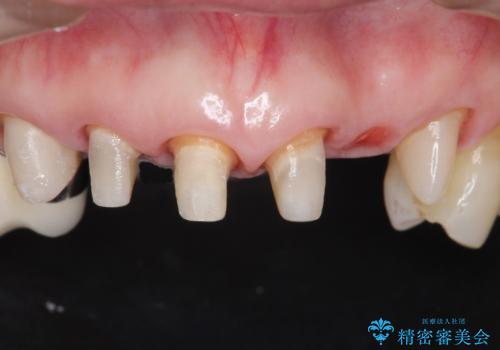

被せ物を除去したところ根管治療後の処置が不十分であったため、ファイバーコア(金属を用いない強くてしなやか材質の土台)を植立したのち、ジルコニアセラミッククラウンによる治療を行いました。

また、古い被せ物はブリッジではない右上321も連結されていましたが、1本1本の歯の動揺がなく連結する必要がないと判断し単冠による補綴を行いました。